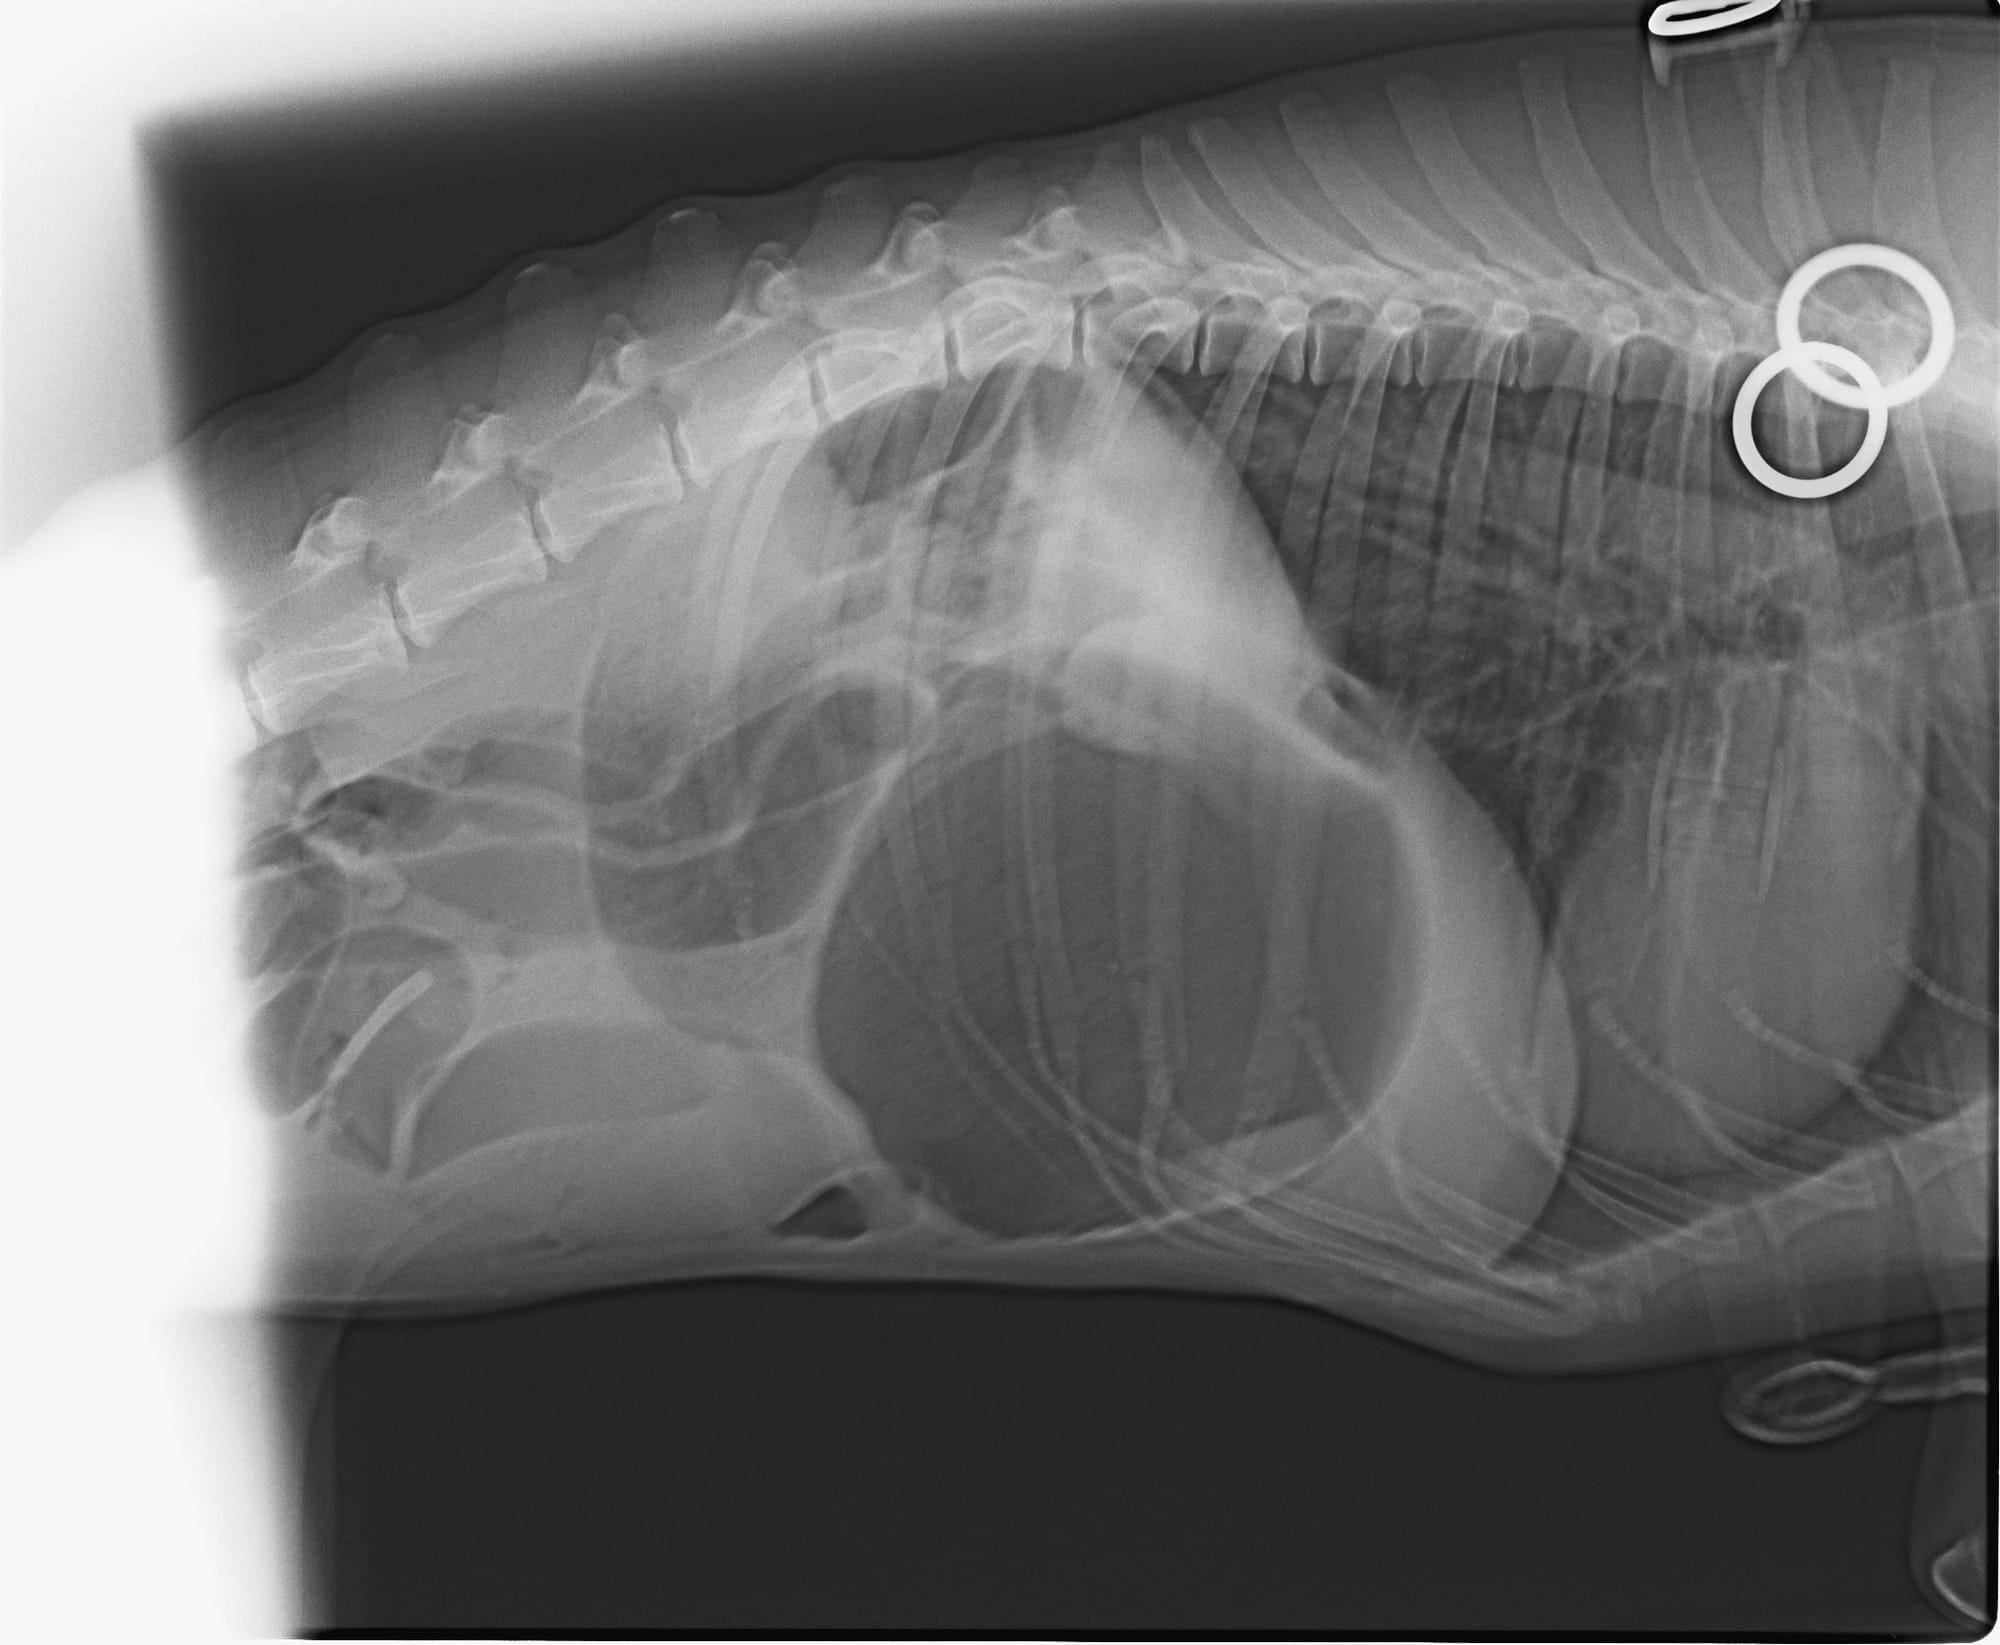

הווטרינר בבית החולים יעשה בדיקה קצרה כדי לאמת את החשד שאכן מדובר בהיפוך קיבה וכדי להעריך את חומרת המצב. לאחר מכן הוא יבצע צילומי רנטגן, ועל ידי כך יגיע לאבחנה אם אכן מדובר בהיפוך קיבה. בהמשך הוא יתחיל ייצוב ראשוני על ידי פתיחת וריד ומתן נוזלים ותרופות.